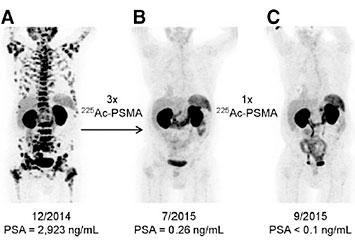

Comparing Indium-111 to Gallium-68 as radioactive tracers in medical scans

(A) SPECT/CT scan using Indium-111 as imaging radioisotope. (B) PET/CT scan using Gallium-68 as imaging radioisotope. Source: J Nucl Med. 2016 Jun; 57(6): 872–878.